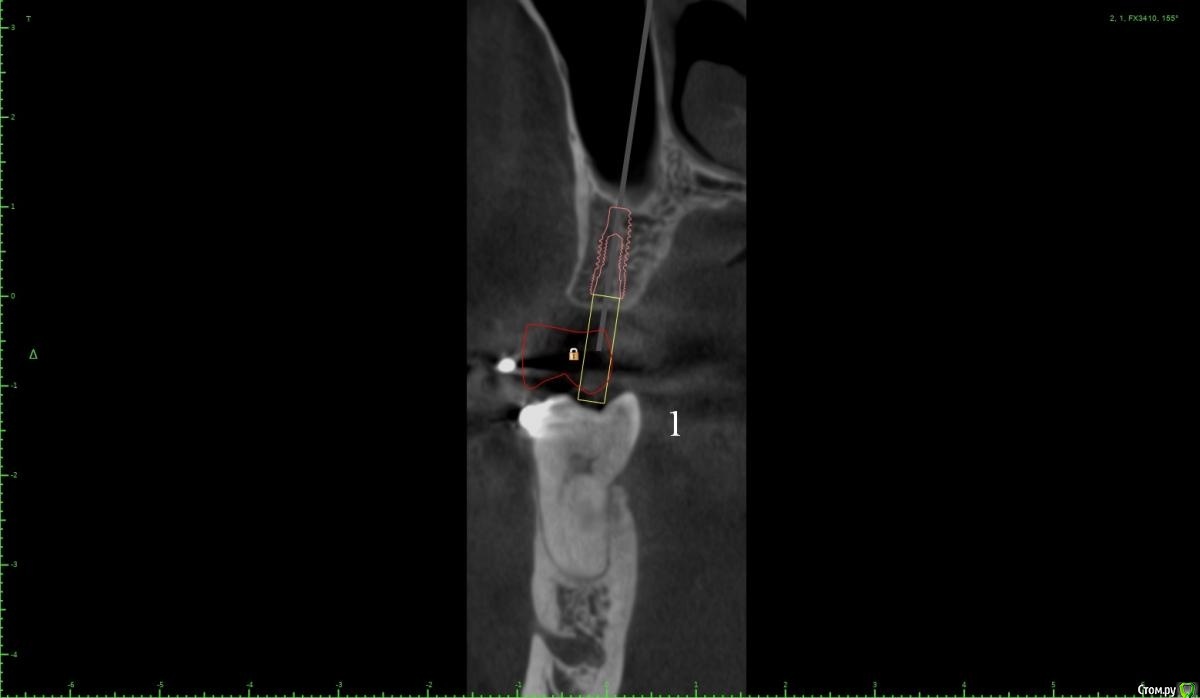

Женька Опубликовано 18 января, 2021 Поделиться Опубликовано 18 января, 2021 (изменено) Коллеги, здравствуйте!Вот такой пациент после орто. Дуги пока на месте, думаем не снимать в области отсутствующих зубов с целью удержать место до этапа протезирования.Вопрос касаемо верхнего винта.Правильно ли я понимаю, что правильным будет именно положение под цифрой 2? Хочу попробовать титановый смарт билдер, как по мне дефект как раз подходит. Или лучше мини сосиску и отсрочено в регенерат ставить. Что думаете? p.s что сверху, что снизу шестые требуют покрытия коронок, отсюда еще один вопрос, стоит ли просить ортодонта стараться ещё ангулировать 46? Просто побаиваюсь, что без этой ангуляции (если ортодонт скажет фи), не удастся сохранить зуб витальным. Ну и бонусом будет поднутрение, не получится адекватно сделать коронку и будет треугольник с едой в этой области. Изменено 18 января, 2021 пользователем Женька Ссылка на комментарий